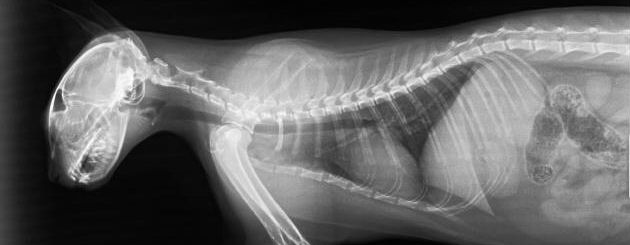

Kleintierpraxis RodenbergIn unserer Kleintierpraxis bieten wir Ihnen allgemeine, tiermedizinische Leistungen auf hohem Niveau an. Aufgrund von fachlicher Spezialisierung und entsprechender technischer Ausstattung der Praxis können Sie zusätzlich spezielle augentierärztliche Untersuchungstermine wahrnehmen. Auf unseren Seiten erhalten Sie nützliche Informationen rund um unsere Praxis, unser Team sowie die Öffnungs- und Sprechzeiten.